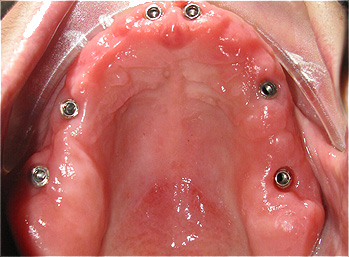

Caso 3 - Desdentado total reabilitado com prótese acrílica removível inferior, barra e clips para retenção e estabilidade

![]() |

![]() ![]() |